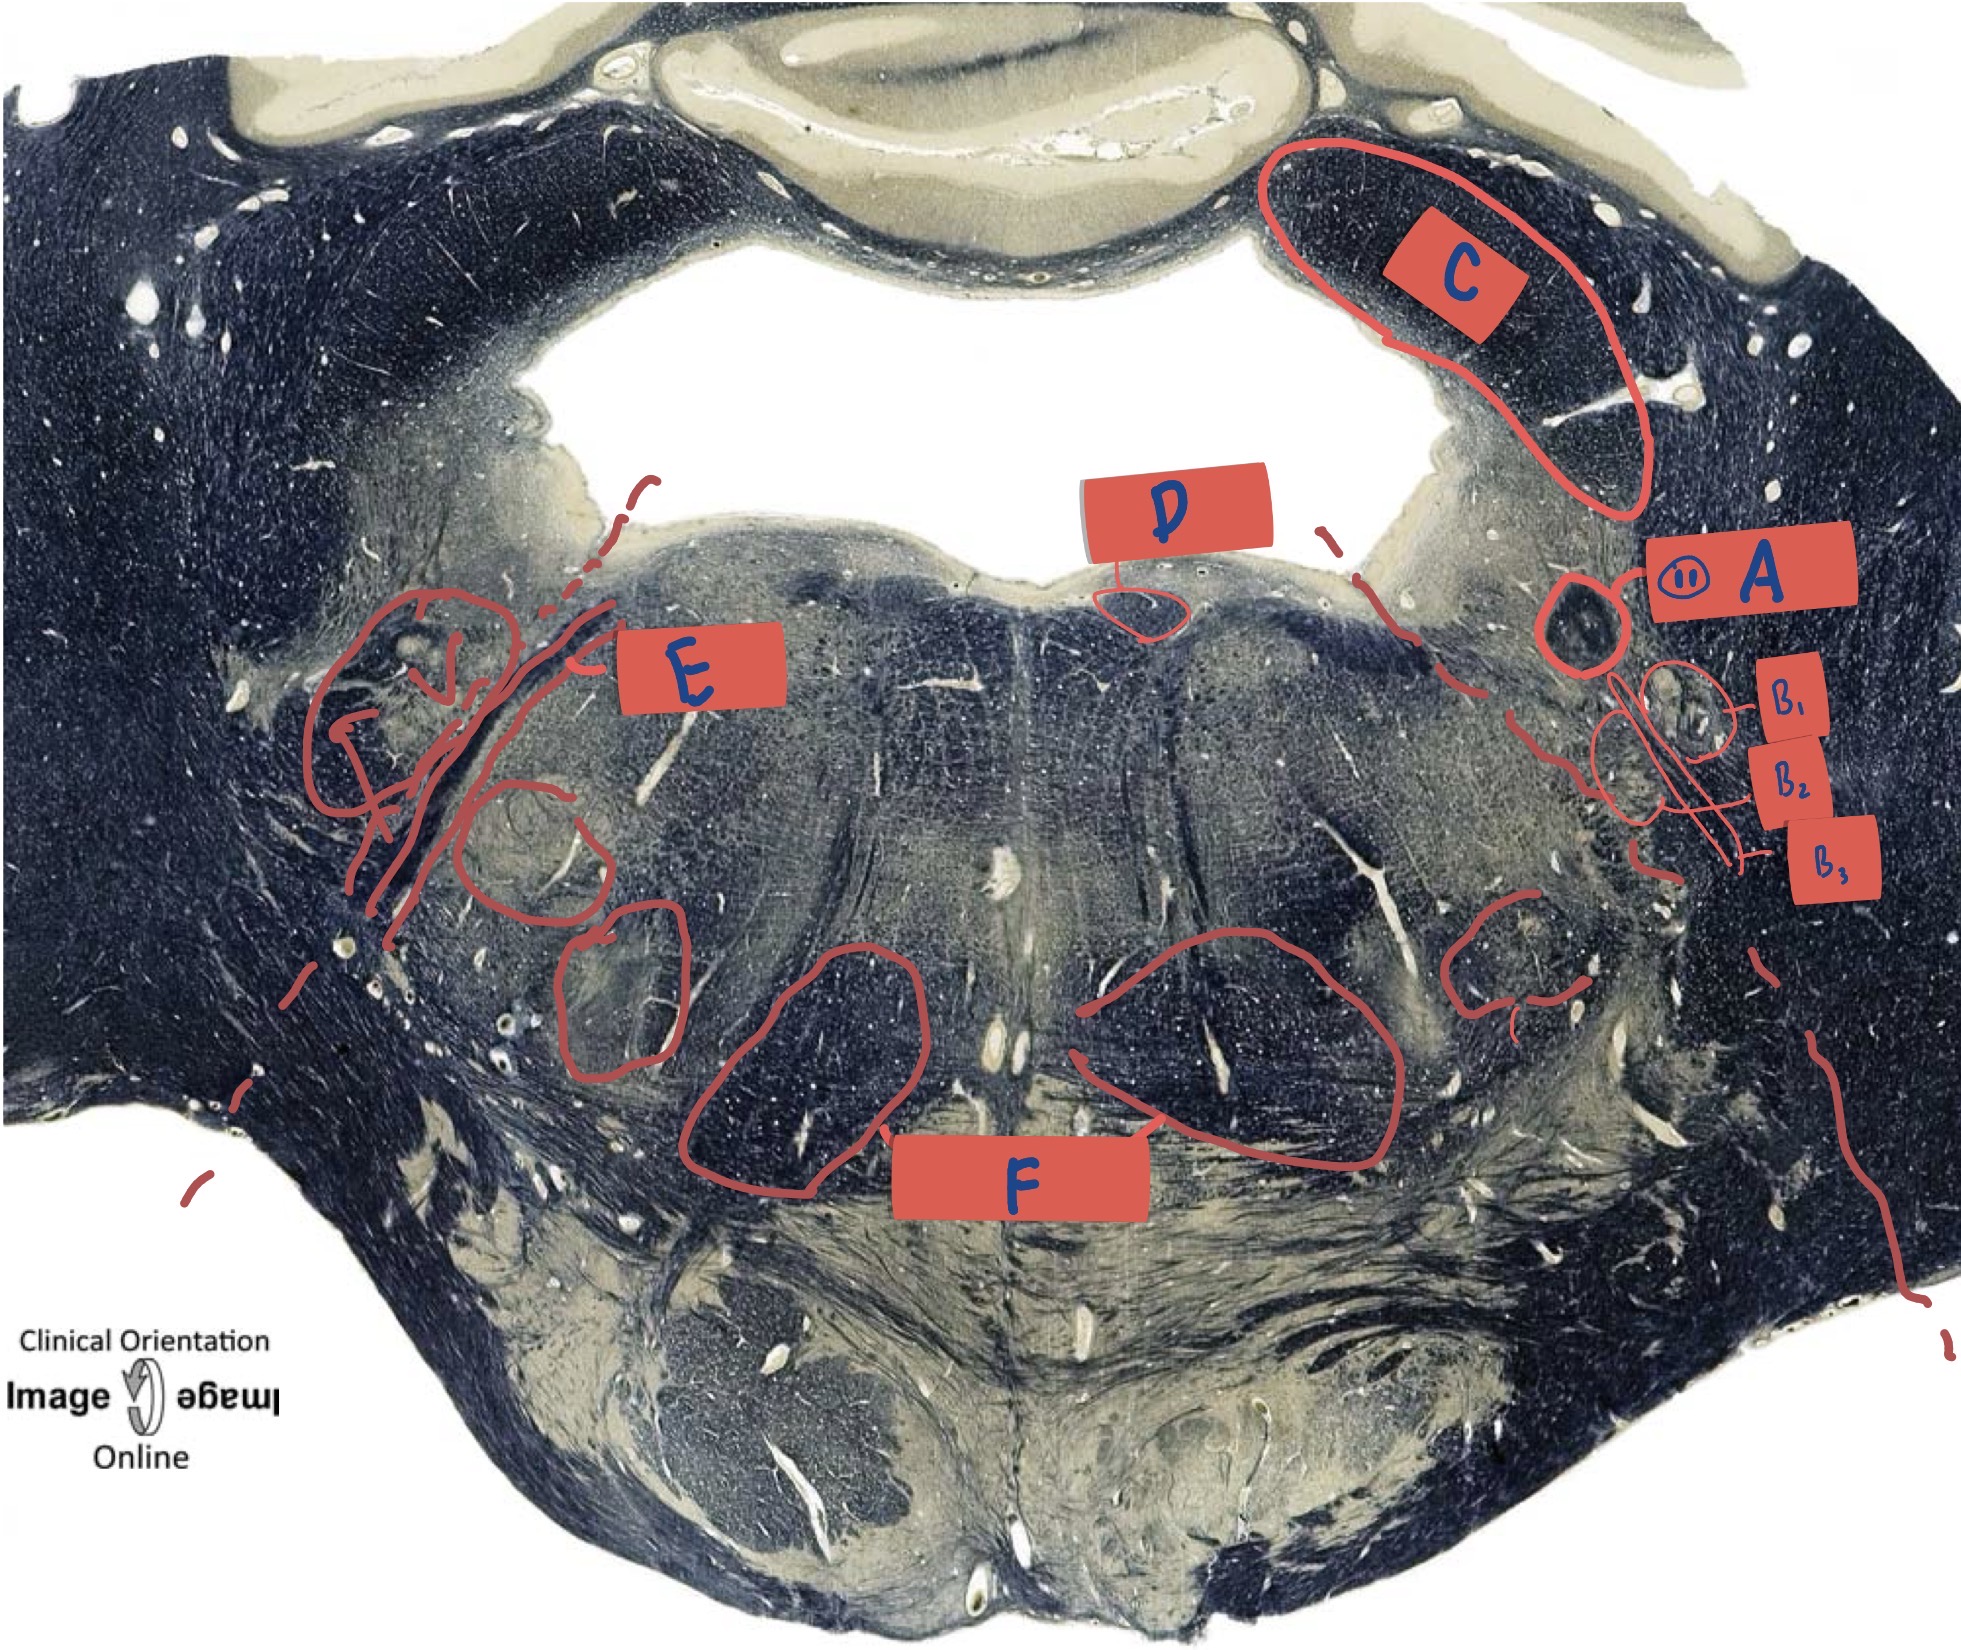

What is A?

Gracile fasticulus

What is B?

Cuneate fasciculus

What is C?

Spinal trigeminal tract

What is D?

Internal Arcuate Fibre

What is E?

Principle olivary nucleus

What is F?

Medial lemniscus